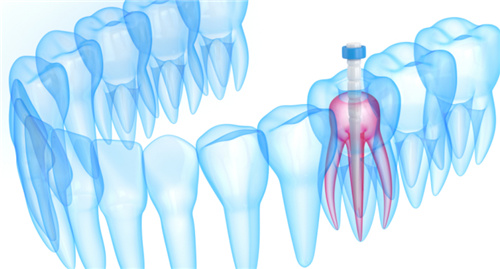

根管治疗是一种用于治疗牙齿神经及周围组织疾病的方法,通常是因为牙髓受损或感染导致牙齿疼痛或其他症状。

在根管治疗完成后,牙齿可能会变得脆弱,容易受到损坏。

而牙冠则是一种覆盖在牙齿表面的人工修复物,旨在加强和保护牙齿,解决其外观和功能。

而戴上牙冠可以有效地加强和保护这颗牙齿,减少进一步的损伤。